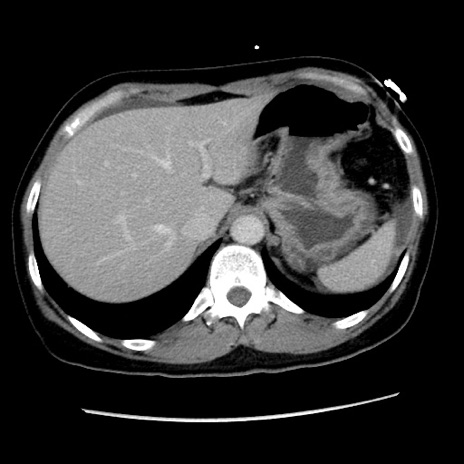

症例10(横断像)

【症例】 50歳代女性

【主訴】 腹痛

【現病歴】前日生レバーを食べた。今朝に排便あり。 昼前に突然発症の腹痛を生じ、当院救急外来を受診した。

【身体所見】 意識清明、腹部:平坦、軟、下腹部やや左を中心に圧痛・反跳痛あり、筋性防御あり